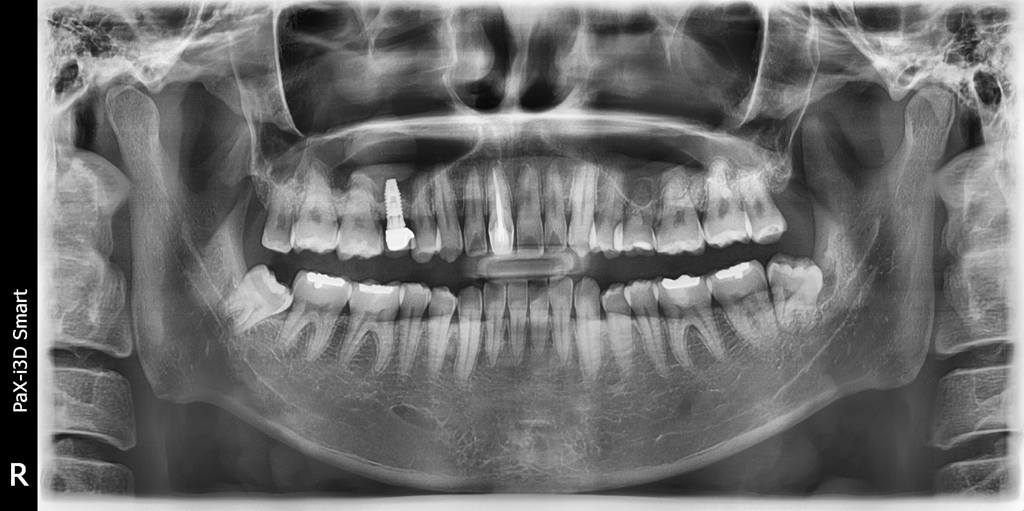

신경치료를 한 치아도 교정은 가능합니다. 단 임플란트를 하신게 잇는데 임플란트는 교정을 하는게 어려워서 일단은 상담을 받아보시는게 좋을것같습니다.